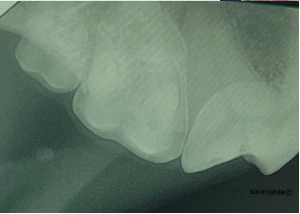

The dental radiograph in Figure 8 is a nondiagnostic image. It is nondiagnostic because the apex of the roots are not included in the image, however, the angle of the image is correct. Therefore, the only change that should be made is a sensor movement.

Once the sensor was moved further into the mouth, in a palatal direction, the entire root structure of right maxillary molars (109/110) are included in the image as well as the distal root of the maxillary fourth premolar (108). (Figure 9a, Figure 9b and Figure 9c) The part of the sensor that could be seen outside of the mouth or beyond the teeth in image (a) corresponds to the black space in the dental radiograph in previous figure. It is important to line up the long side of the sensor with the cusp of the tooth/teeth to ensure the entire senor is used. This sensor placement is similar to collimating full body radiographs: ensuring all the target anatomy is within the radiograph.